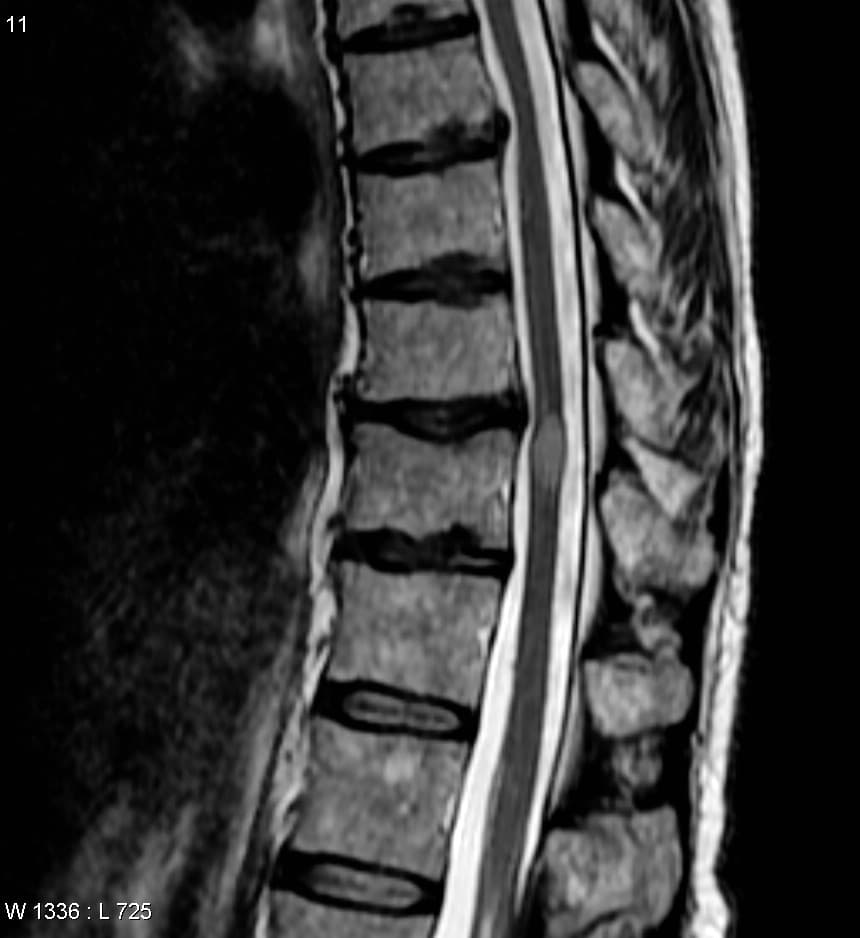

La myélite transverse (MT) est un syndrome neurologique traduisant une inflammation de la moelle spinale pouvant toucher l'adulte comme l'enfant. Son étiologie est encore mal comprise, mais semble principalement auto-immune car elle survient souvent après une infection virale (herpès, mycoplasme, EBV, CMV, VIH...) ou un vaccin, ce qui laisse penser qu'il s'agit d'une "mauvaise" réaction de l'organisme qui au lieu de protéger ses cellules se retourne contre certaines d'entre elles. Ce syndrome est classé parmi les maladies neuroimmunologiques du système nerveux central (comme l’encéphalomyélite aiguë disséminée (EMAD), la névrite optique, et la neuromyélite optique, aussi dénommée maladie de Devic. C'est une maladie rare avec un à cinq cas par million dans la population générale selon les estimations étudiées par Jeffery en 1993. Elle n'affecte qu'une partie de la moelle, avec donc des symptômes habituellement bilatéraux dont la nature dépendra de l'étendue et de la localisation des lésions inflammatoires. La myélite transverse aiguë (ou MTA) idiopathique, d'étiologie encore inconnue est une maladie immunitaire inflammatoire démyélinisante de la moelle spinale présentant des manifestations motrices, sensitives et autonomiques (incidence annuelle : estimée entre 1/ et 1/, selon les études). Elle est souvent précédée d'une virose (trois semaines plus tôt), concernant souvent les voies respiratoires supérieures, faisant évoquer . Le mot « myélite » désigne de manière non spécifique toute inflammation de la moelle spinale. Les poussées inflammatoires peuvent endommager ou détruire la myéline qui recouvre les neurones, et la cicatrisation de ces lésions peut interrompre la communication entre une partie des nerfs de la moelle spinale et le reste du corps. L'adjectif « transverse » évoque le fait que cette maladie touche tout le plan horizontal (traverse de droit à gauche )de la moelle epiniere , mais elle touche juste un segment de la moelle le plus souvent thoracique ,moins frequemment lombaire et cervicale Le terme médical myélopathie est parfois aussi utilisé ; il est plus général, désignant n'importe quelle atteinte de la moelle.